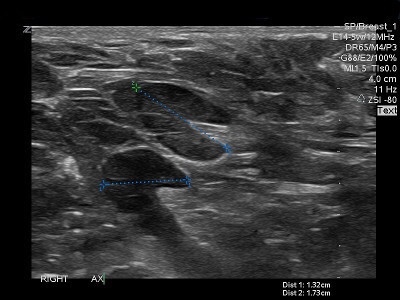

👉Another presentation of a metastatic node is an asymmetric cortex where the tumor can be seen invading the hilum with convex indentations that look like “rat bites” (Image).

👉A metastatic node can also have severe compression of a central hilum resulting in a slit-like central hyperechoic band (Image).